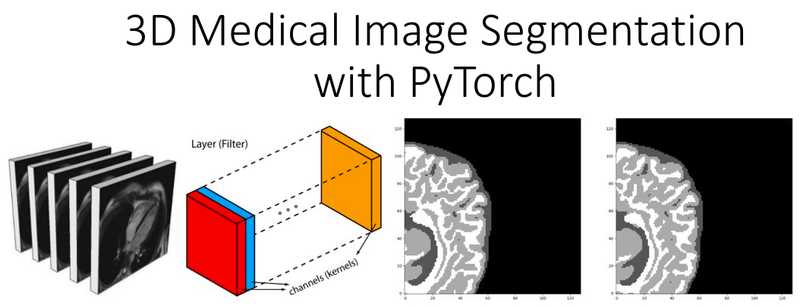

Understanding coordinate systems and DICOM for deep learning cheap, DICOM Imaging Router An Open Deep Learning Framework for cheap, Processing Computer Tomography CT for Deep Learning Applications cheap, Dicom Deep Learning 2024 www.chop rite cheap, Dicom Deep Learning 2024 www.chop rite cheap, Annotate DICOM images and build an ML model using the MONAI cheap, A DICOM Framework for Machine Learning and Processing Pipelines cheap, 4 tips on DICOM handling in Machine Learning for Healthcare cheap, Architecture of the web viewer for WSI images in DICOM format with cheap, Dicom Deep Learning 2024 www.chop rite cheap, DICOM Latest Advances in AI ML Applied to Medical Imaging cheap, Schematic of data flow for deep learning framework operation cheap, Dicom Deep Learning 2024 www.chop rite cheap, Medical Image Segmentation A Complete Guide Encord cheap, Deep Learning driven classification of external DICOM studies for cheap, Dicom Systems De identifies 5.3 Million Radiology Exams cheap, Three dimensional deep learning to automatically generate cranial cheap, Deep learning assesses additional radiation dose in overscanning cheap, Medical Image Analysis with Deep Learning Part 4 KDnuggets cheap, GitHub ben heil DICOM CNN Convolutional neural network solution cheap, Transfer Learning for Dicom Image Classification cheap, Encoding of machine learning model outputs in DICOM. A Information cheap, Introduction to 3D medical imaging for machine learning cheap, Dicom Deep Learning 2024 www.chop rite cheap, Diagnostics Free Full Text Deep Semi Supervised Algorithm for cheap, TWIMLfest Fundamentals of Medical Image Processing for Deep Learning cheap, Free software for deep learning medical image annotation cheap, A Machine Learning method for relabeling arbitrary DICOM structure cheap, Building Scalable Machine Learning Pipelines for Multimodal Health cheap, 10 Best DICOM Viewers for Medical Images 2023 Update cheap, GitHub Mattobad Pneumonia Detection Deep Learning Applying deep cheap, Deep learning in medical imaging 3D medical image segmentation cheap, Processing medical images data files for deep learning cheap, Lung Cancer Detection and Classification on DICOM Dataset cheap, Dicom Deep Learning 2024 www.chop rite cheap.

Understanding coordinate systems and DICOM for deep learning cheap, DICOM Imaging Router An Open Deep Learning Framework for cheap, Processing Computer Tomography CT for Deep Learning Applications cheap, Dicom Deep Learning 2024 www.chop rite cheap, Dicom Deep Learning 2024 www.chop rite cheap, Annotate DICOM images and build an ML model using the MONAI cheap, A DICOM Framework for Machine Learning and Processing Pipelines cheap, 4 tips on DICOM handling in Machine Learning for Healthcare cheap, Architecture of the web viewer for WSI images in DICOM format with cheap, Dicom Deep Learning 2024 www.chop rite cheap, DICOM Latest Advances in AI ML Applied to Medical Imaging cheap, Schematic of data flow for deep learning framework operation cheap, Dicom Deep Learning 2024 www.chop rite cheap, Medical Image Segmentation A Complete Guide Encord cheap, Deep Learning driven classification of external DICOM studies for cheap, Dicom Systems De identifies 5.3 Million Radiology Exams cheap, Three dimensional deep learning to automatically generate cranial cheap, Deep learning assesses additional radiation dose in overscanning cheap, Medical Image Analysis with Deep Learning Part 4 KDnuggets cheap, GitHub ben heil DICOM CNN Convolutional neural network solution cheap, Transfer Learning for Dicom Image Classification cheap, Encoding of machine learning model outputs in DICOM. A Information cheap, Introduction to 3D medical imaging for machine learning cheap, Dicom Deep Learning 2024 www.chop rite cheap, Diagnostics Free Full Text Deep Semi Supervised Algorithm for cheap, TWIMLfest Fundamentals of Medical Image Processing for Deep Learning cheap, Free software for deep learning medical image annotation cheap, A Machine Learning method for relabeling arbitrary DICOM structure cheap, Building Scalable Machine Learning Pipelines for Multimodal Health cheap, 10 Best DICOM Viewers for Medical Images 2023 Update cheap, GitHub Mattobad Pneumonia Detection Deep Learning Applying deep cheap, Deep learning in medical imaging 3D medical image segmentation cheap, Processing medical images data files for deep learning cheap, Lung Cancer Detection and Classification on DICOM Dataset cheap, Dicom Deep Learning 2024 www.chop rite cheap.